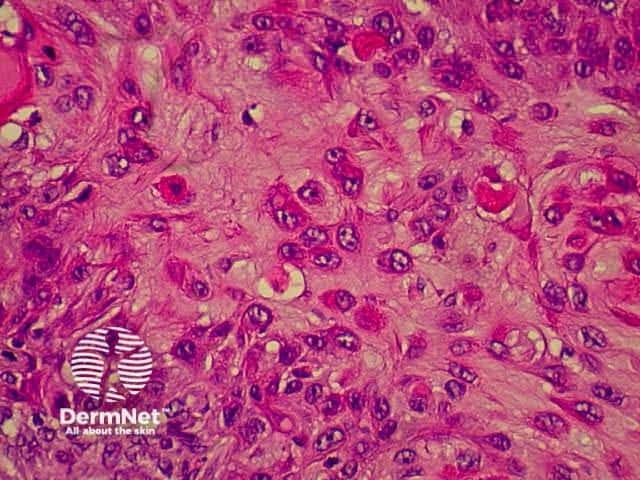

SCC is characterised by proliferation of irregular nests of abnormal squamous cells arising from the epidermis and invading the dermis. Tumours are traditionally divided into well, moderately or poorly differentiated tumours by a subjective assessment of how significantly the tumour cells differ from normal keratinocytes. In general, the greater the degree of keratinization, the better differentiated the tumour is thought to be. Except in the case of very poorly differentiated tumours, this does not have a great bearing on prognosis. More important is the depth and irregularity of invasion, particularly the presence of perineural infiltration, which is associated with a much higher rate of recurrence if not widely excised. The site of the lesion is also important; tumours of the lips and ears have a considerably higher rate of metastasis to lymph nodes.

From the above comments it can be seen that the histological features of SCCs can vary, but in general are:

Pathology of SCC Pathology of SCC Pathology of SCC Pathology of SCC